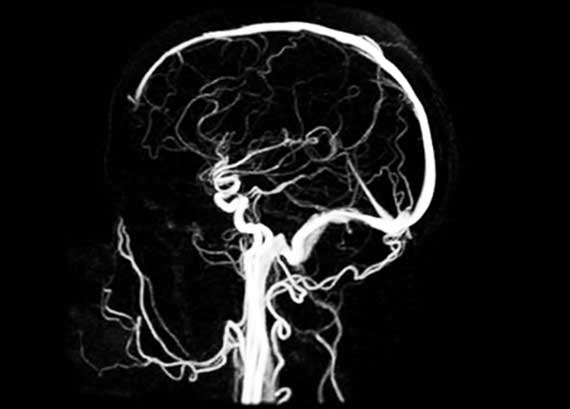

Магнитно-резонансная ангиография – МРА

МРА или магнитно-резонансная ангиография – это информативный и безопасный метод лучевой диагностики, не использующий рентгеновского излучения, позволяет составить 3-д картину сосудистого русла головного мозга.

МР ангиографию артерий головного мозга проводят без контраста – это несомненное преимущество.